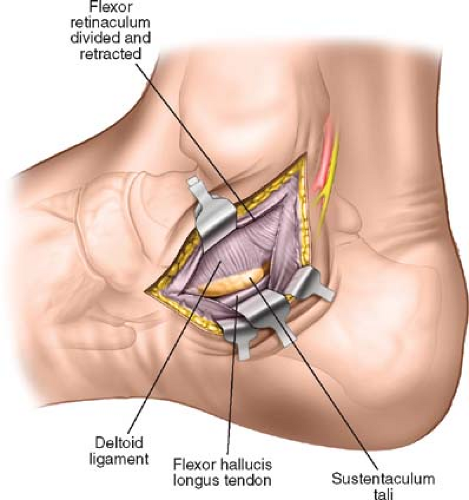

what are the medial ligaments of the deltoid ligament?

anterior tibiotalar

tibionavicular

tibiocalcaneal

posterior tibiotalar

what is the deltoid ligament?

what does the deltoid ligament do?

restrict eversion

sustentaculum tali

what is the sustentaculum tali?

shelf of calcaneus where tali sits on